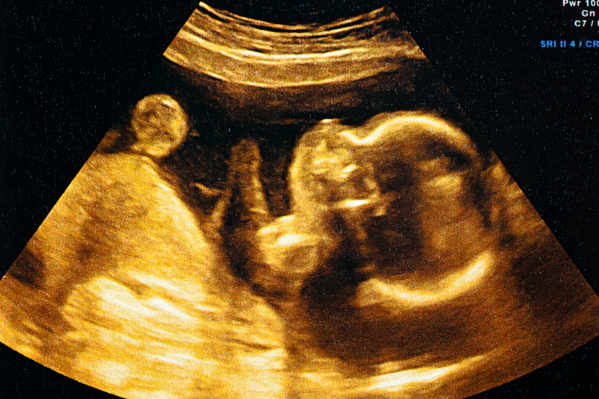

Technologie en chirurgie

Opérer in utero

Cécile Guérin se penche sur une intervention particulière et très délicate: l'opération in utero sur des fœtus.

Lire la suite